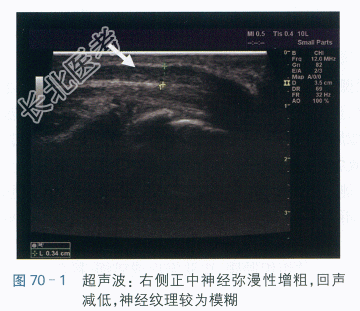

超声波检查显示:右侧腕部区域正中神经弥漫性增粗,回声减低,神经纹理较为模糊,豌豆骨水平横切面约11mm²,如图70-1和图70-2所示。